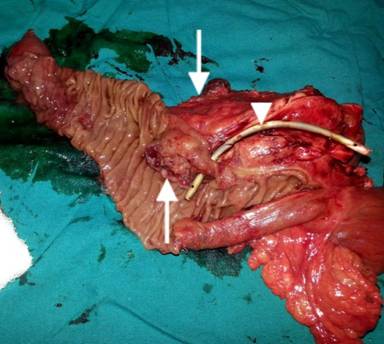

Patient underwent surgery, where a large mass of size 3 cm was found in the periampullary region with absence of body and tail of the pancreas confirming the diagnosis of agenesis of dorsal pancreas. A total pancreatectomy, duodenectomy, Roux-en-Y gastrojejunostomy, hepaticojejunostomy, and cholecystectomy were performed. On gross examination, a large ulceroinfiltrative lesion (3.0×2.5×2.0 cm) involving mostly periampullary region was found which was firm in consistency, pale greyish white in appearance with ill defined edges appearing to invade almost full thickness of the duodenal wall extending onto subserosa (Figure 3). Histopathological examination revealed invasive poorly differentiated adenocarcinoma with diffuse deep infiltration involving almost full thickness of the duodenal wall and invading subserosa (Figure 4a). Immunohistochemistry was done and the tumor cells were positive for immunohistochemical markers CA 19-9 (Figure 4b), cytokeratin-7, KI-67 (Figure 4c) and negative for CEA, cytokeratin-20. No lymph node metastasis was found.

Figure 3. Resected specimen showing the periampullary mass (upward arrow), CBD stent in situ (arrow head) and pancreas (downward arrow). |